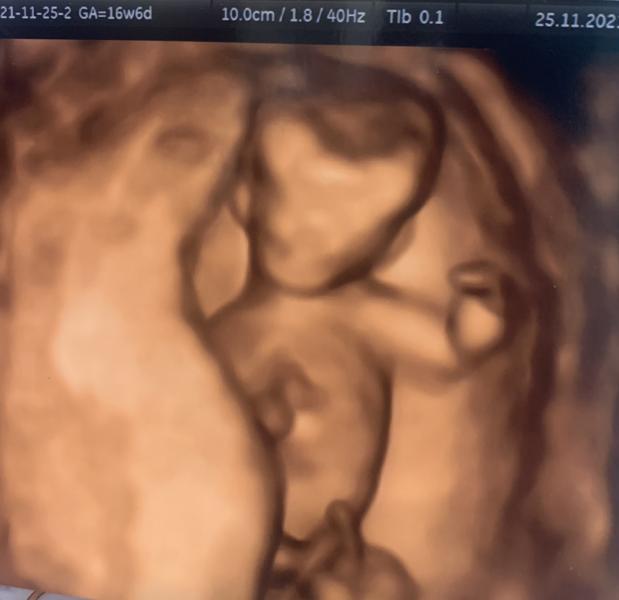

Первый скрининг прошёл хорошо☺️… с малышом все отлично.. все узи руками, ногами махал.. пол не удалось узнать.. пуповина между ног.. один минус предлежание плаценты.. ну не чего поднимется 🥰

Тоже низкое ставили, на втором скрининге опять низкое, говорят до родов ещё поднимется, почему на фото кажется что это мальчик(это просто мне так кажется) 😌